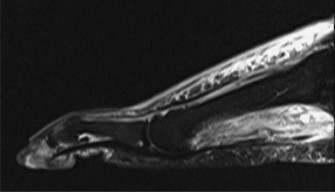

- Intraoperative view demonstrating the completed transverse tenotomy of the gastrocnemius aponeurosis, revealing the underlying intact soleus fascia and the created gap that allows for increased ankle dorsiflexion.